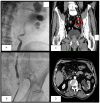

Myeloid sarcoma (MS) is an extramedullary tumor mass causing proliferation of mature or immature blast cells of one or more myeloid lineages. Involvement of the genitourinary tract is rare. We present a case of MS of the ureteral wall. A 74-year-old man was evaluated for left hydronephrosis and ipsilateral low back pain. A computed tomography scan showed a nodular formation in the pelvic ureter. Urinary cytology revealed cellular atypia, so ureteroscopy was performed showing a distal ureteral mass. The histological examination of the biopsy revealed to be malignant neoplasm. The patient underwent left laparoscopic nephroureterectomy with bladder cuff excision. Microscopic histological examination revealed a tumor compatible with MS. A postoperative positron emission tomography revealed residual hypercaptation of the bladder, pelvic muscle and iliac nodes, so the patient started chemotherapy. A multidisciplinary approach was required, taking into account the patient's age, the already poor renal function and the location of the neoplasm.